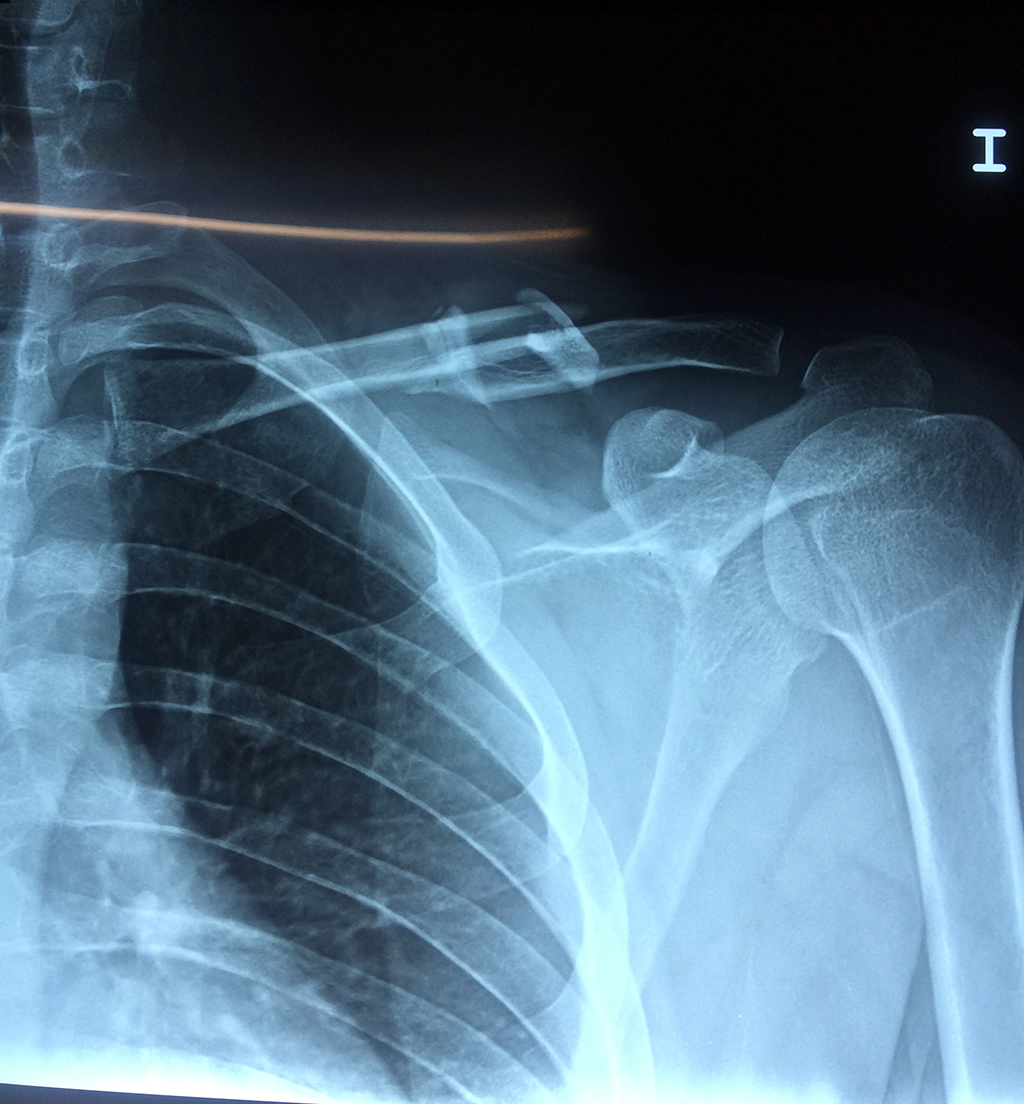

Cirugías de Codo - Clavícula

La clavícula es un hueso largo, con forma de "S" itálica, situado en la parte anterosuperior del tórax. Junto con la escápula forman la cintura escapular. Se puede palpar por toda su longitud y se extiende del esternón al acromion de la escápula, siguiendo una dirección oblicua lateral y posterior.

Se considera el único medio de unión entre el miembro superior y el tórax. A pesar de su aspecto, similar al de un hueso largo, posee una estructura semejante a la de un hueso plano, ya que carece de epífisis y de diáfisis, lo que la harían entrar dentro de la clasificación de hueso largo. Carece de un canal medular propiamente dicho.